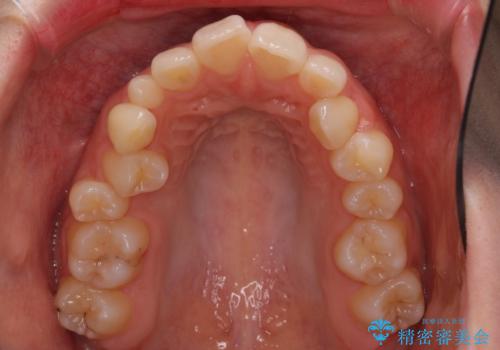

狭い上顎骨を拡大 急速拡大装置を併用したインビザライン矯正

- 前歯のクロスバイトや残存している乳歯を気にして来院された患者様です。

上顎骨の幅が下顎骨よりも小さいので、拡大装置により骨幅を広げて上下関係を改善し、その後インビザラインにて歯並びを整えることとしました。

上下の骨幅を改善したことで、スムーズに歯列矯正を行うことができました。